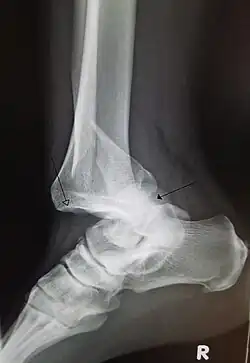

Dislocation of the left index finger -

Radiograph of right fifth phalanx bone dislocation -

Radiograph of left index finger dislocation